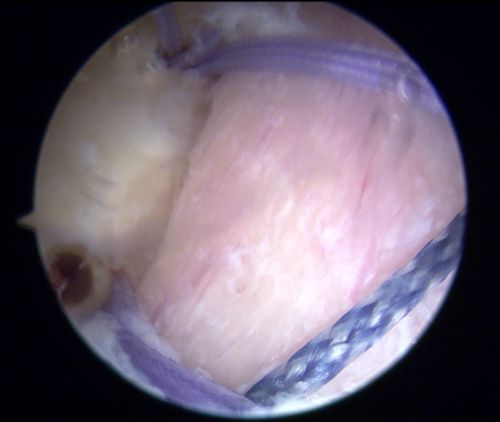

巨大的断崖式缺损部位。

由于左肩脱位症状极重,患者入院当天早上再次发生脱位。CT检查发现,左肩胛盂有较大的骨缺损,缺损面积大约为15X35mm,相当于正常肩胛盂面积的30%。目前,针对此类肩胛盂(骨缺损>20%)修复,指南建议使用临近的喙突移植肩胛骨以修补骨性缺损(Lartarjet术),但不幸的是患者喙突发育不良,小于骨缺损体积,Lartarjet术没有条件实施。王靖果断决定利用髂骨来修复肩胛盂。该手术在关节镜下实施难度极大,是省内首次报道,同时也为肩关节脱位合并巨大肩胛盂缺损患者提供了肩关节镜微创治疗的新方法。术后复查CT可见左肩胛盂前方有一块移植髂骨块挡住了肱骨头脱位的轨迹。